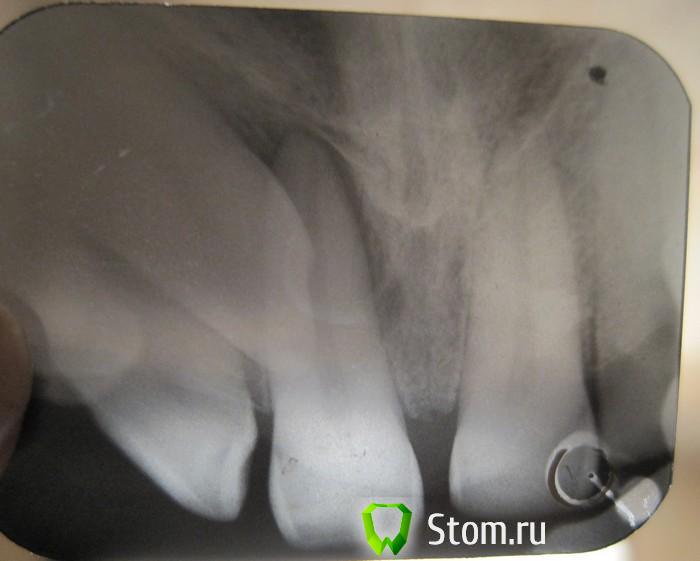

Мармышка Опубликовано 21 января, 2012 Автор Поделиться Опубликовано 21 января, 2012 вот ещё попыталась в домашних условиях сфотографировать дентальные снимки. Первый снимок до лечения и дот панорамника, второй- после. Извиняюсь за качаство) Ссылка на комментарий

kriokov Опубликовано 21 января, 2012 Поделиться Опубликовано 21 января, 2012 почему именно вестибулярно? у меня тоже такая мысль была, но он говорит, что нёбо болит...когда дело касается наших близких, все мысли куда-то улетучиваются(((сложно сказать как он лежит, оба снимка практически в одной проекции. Чтобы по правилу щечного обекта определиться надо второй снимок делать в эксцентричной проекции. Ссылка на комментарий

kriokov Опубликовано 21 января, 2012 Поделиться Опубликовано 21 января, 2012 +1 за вестибулопозицию клыка. Прежде чем удалять посоветуйтесь с ортодонтом. думаю вытянуть будет вернеза небное положение, по анализу ОПТГ. Размеры коронки ретенированного клыка увеличены в размере и растянуты, а корень нет, значит обьект (коронка) близко к фокусу- т.е небно Ссылка на комментарий